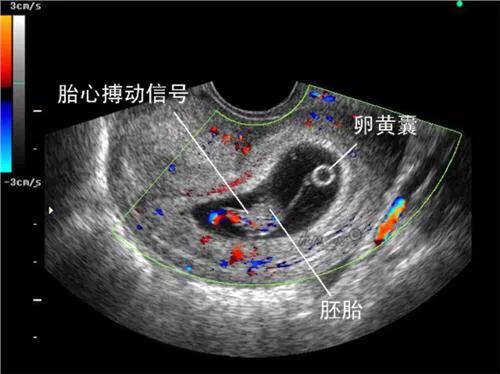

看胚胎发育情况:5-6周可见孕囊,6-7周可见胎芽胎心

胎心和血流:孕6周B超能见胎心搏动,120-160次/分钟;如果做了CDFI彩色多普勒血流显像,显示有胎囊血流信号,则胎儿健康;